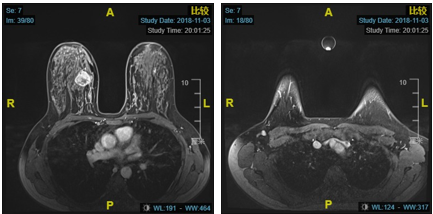

影像学检查

•  2018.11.7我院CT:右侧腋窝见强化小淋巴结。两肺目前未见明显活动性病变。

•  2018.11.5我院乳腺MRI:右乳内上肿块,符合恶性肿瘤表现,BI-RADS 6。

2疗程治疗后评估:PR

右乳癌治疗后较前好转,右乳头后方导管扩张同前,BI-RADS:6。 右腋下小淋巴结同前。左乳未见明显异常,BI-RADS:1

4疗程治疗后评估:CR

4疗程后MRI:右乳癌治疗后较前好转,BI-RADS:6。 右腋下小淋巴结同前